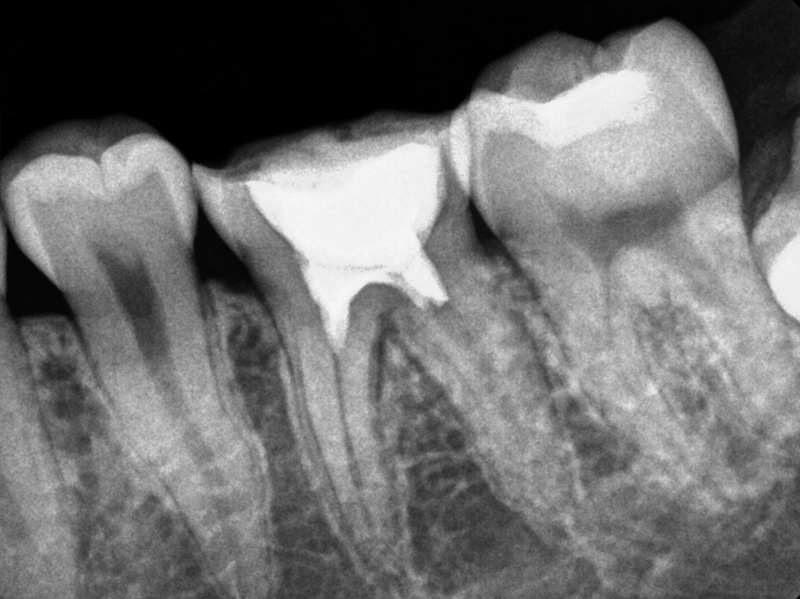

기존 신경치료

생활치수치료

기존 신경치료 vs 생활치수치료

신경조직을 뿌리 끝까지 제거 시술법 세균이 침투한 부위까지만 신경조직 제거

재신경치료는 기존에 신경치료로 충전한 재료를 모두 제거하고 신경치료를 다시 하는 술식으로,

신경치료에 비해 난이도가 높지만 치아를 보존할 수 있는 중요한 술식입니다.